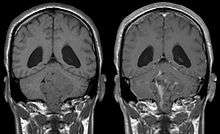

Ependymoma is a tumor that arises from the ependyma, a tissue of the central nervous system. Usually, in pediatric cases the location is intracranial, while in adults it is spinal. The common location of intracranial ependymoma is the fourth ventricle. Rarely, ependymoma can occur in the pelvic cavity.

Ependymomas make up about 5% of adult intracranial gliomas and up to 10% of childhood tumors of the central nervous system (CNS). Their occurrence seems to peak at age 5 years and then again at age 35. They develop from cells that line both the hollow cavities of the brain and the canal containing the spinal cord, but they usually arise from the floor of the fourth ventricle, situated in the lower back portion of the brain, where they may produce headache, nausea and vomiting by obstructing the flow of cerebrospinal fluid. This obstruction may also cause hydrocephalus. They may also arise in the spinal cord, conus medularis and supratentorial locations.[4] Other symptoms can include (but are not limited to): loss of appetite, difficulty sleeping, temporary inability to distinguish colors, uncontrollable twitching, seeing vertical or horizontal lines when in bright light, and temporary memory loss. It should be remembered that these symptoms also are prevalent in many other illnesses not associated with ependymoma.

About 10% of ependymomas are benign myxopapillary ependymoma (MPE). MPE is a localized and slowly growing, low-grade tumor. Although some ependymomas are of a more anaplastic and malignant type, most of them are not anaplastic. Well-differentiated ependymomas are usually treated with surgery. For other ependymomas, total surgical removal is the preferred treatment in addition to radiation therapy. The malignant (anaplastic) varieties of this tumor, malignant ependymoma and the ependymoblastoma, are treated similarly to medulloblastoma but the prognosis is much less favorable. Malignant ependymomas may be treated with a combination of radiation therapy and chemotherapy. Ependymoblastomas, which occur in infants and children younger than 5 years of age, may spread through the cerebrospinal fluid and usually require radiation therapy. The subependymoma, a variant of the ependymoma, is apt to arise in the fourth ventricle but may occur in the septum pellucidum and the cervical spinal cord. It usually affects people over 40 years of age and more often affects men than women.